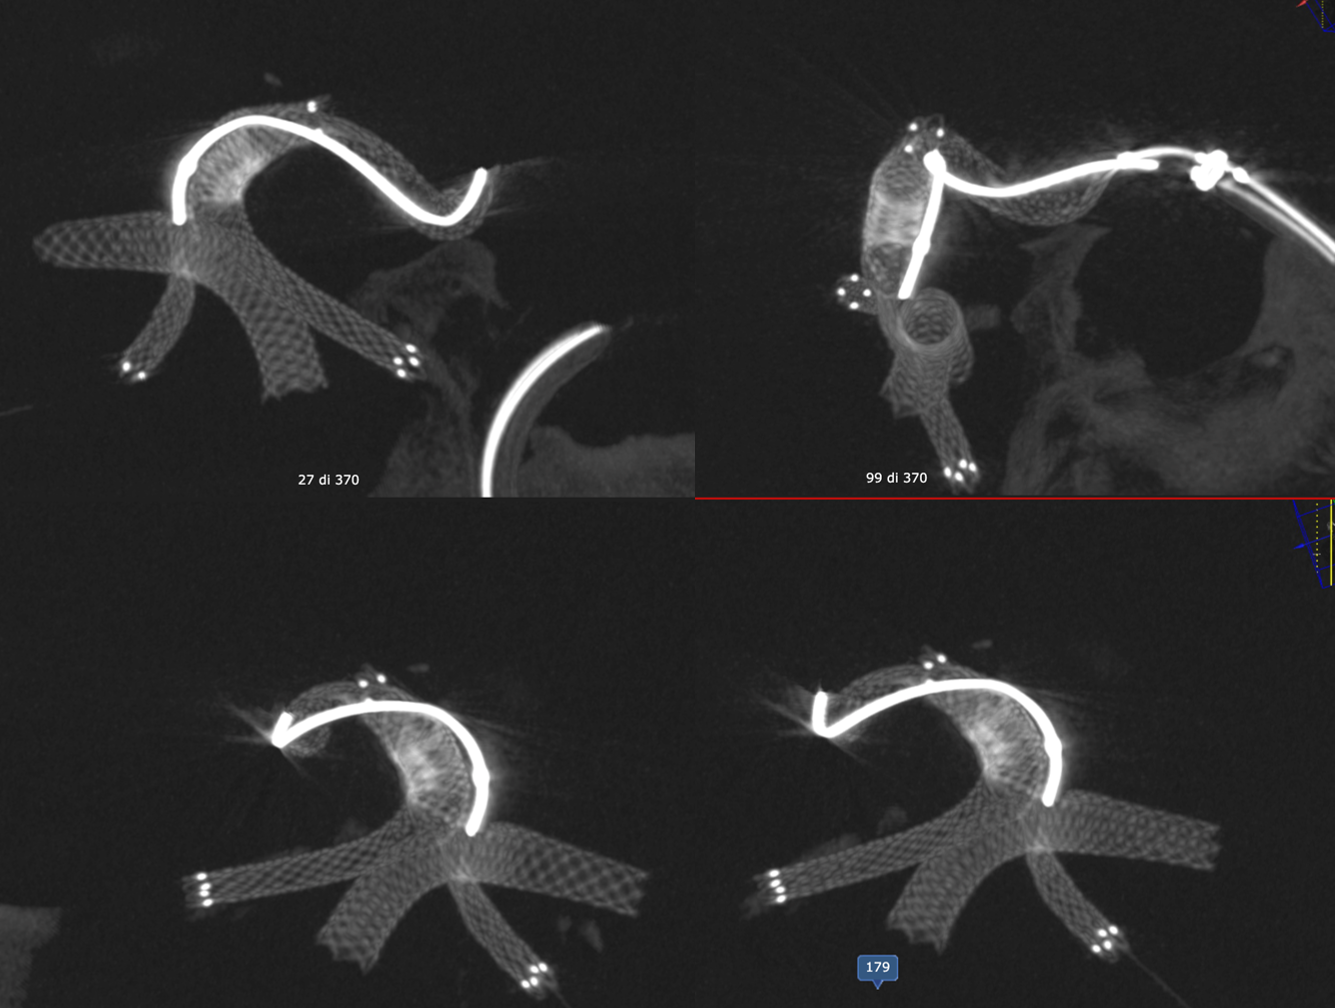

Noncontrast Vaso-CT, 22 cm FOV 20 seconds acquisition, followed by a secondary reconstruction with 50% FOV and 5123 resolution; Thick MIP.

Wide neck MCA trifurcation aneurysm.

Y stenting with Atlas and Lvis Evo, in emergency. The Atlas diameter was too large because of the temporary limited availability in our centre; we can clearly see the struts of the Atlas too open at the level of the aneurysm neck (arrow). Even the microcatheter for coiling is fully visible jailed by the Lvis Evo in M1

The injection of contrast medium (250 mg/ml, 50% dilution, manual injection, same reconstruction protocol as previous images) reduces the visibility of the struts — an important point to consider. Not everything is always the same contrast dilution, same injection rate, etc. etc. — you need to know how to vary every parameter to achieve desired results.